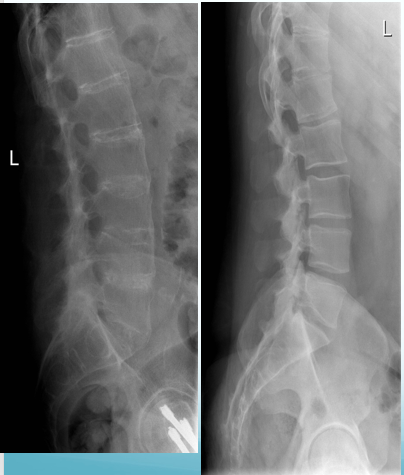

100% of people over 65 years have radiological changes in their spines. What are examples of these changes?